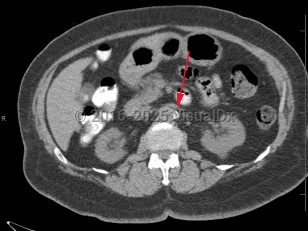

Renal artery stenosis

Renal artery stenosis is narrowing or blockage of renal artery / arteries. Causes include atherosclerosis, fibromuscular dysplasia, thrombosis, embolism, or external pressure. Reduced renal perfusion can lead to renovascular hypertension as well as acute or chronic kidney injury.